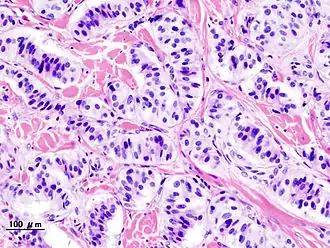

Description de l'image Pancreatic insulinoma (2).JPG.

Le nésidioblastome, est une tumeur pancréatique langerhansienne. Elle fait partie des tumeurs neuroendocrines.